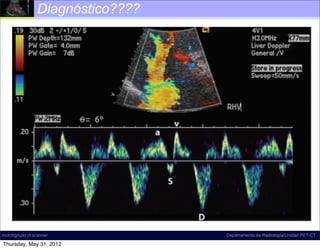

Diagnóstico????

Insuficiencia tricuspídea

moderada (S < D, >>> a/v)

Insuficiencia tricuspídea grave

moderada (S <onda S) a/v)

(inversión D, >>>